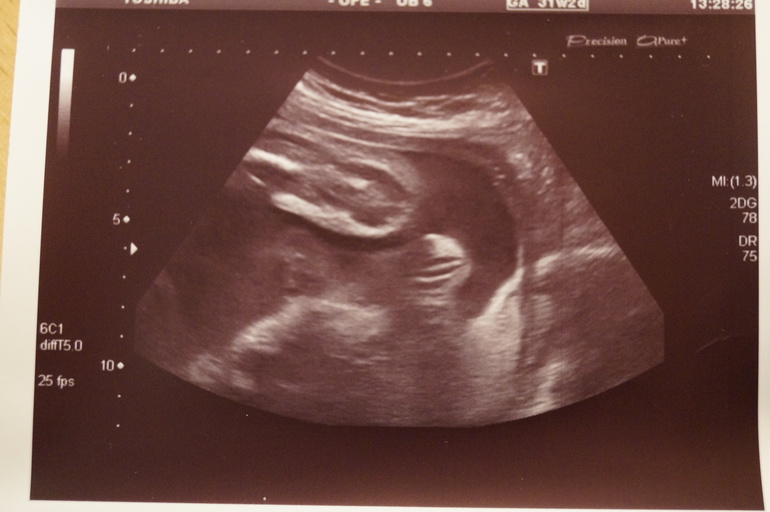

Дня три назад мне показалось, что наша доча стала спокойнее себя вести. И, как полагается нам беременным, в голову полезли нехорошие мысли... Вдруг ей там плохо, вдруг гипоксия? Оговорюсь сразу, что на узи с доплером я записана на 18 февраля, а 19 на приём к врачу. 31 января моя писюха не дала сделать КТГ. Убежала от датчика и он не смог дать заключение. 19 будем переделывать. Так вот. Вчера с мужем посовещались и я решила, что сегодня запишусь на внеплановое узи. Утром позвонила в клинику и, О ЧУДО!!!!! , оказалось есть свободное время. Пришла. Слава Богу, всё у нас хорошо. Всё по срокам. Доплер хороший. Все кровотоки хорошие. Я понимаю, что ей там места мало становится, может из-за погоды спокойнее стала... Но вы, девочки, ведь меня поймёте..... А вдруг есть какие-то нарушения? Уж лучше о них узнать раньше и успеть что-то предпринять. Ну вот наши результаты. В этот раз ходила одна. Без мужа.

Ну, и по традиции фотки нашей зайки...